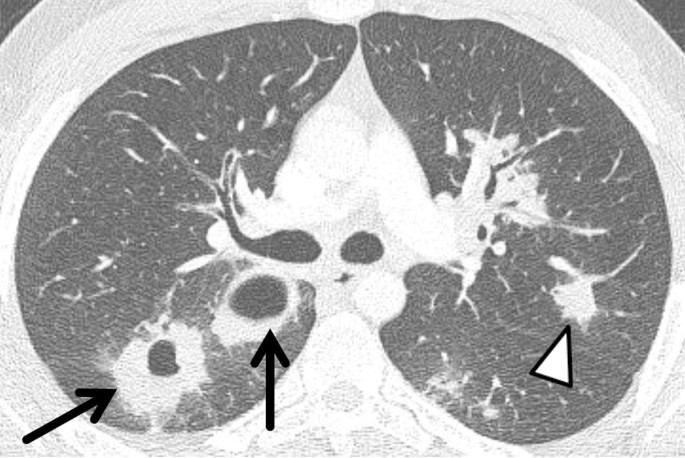

Figure 1 Granulomatose Lungen Und Systemerkrankungen Springerlink